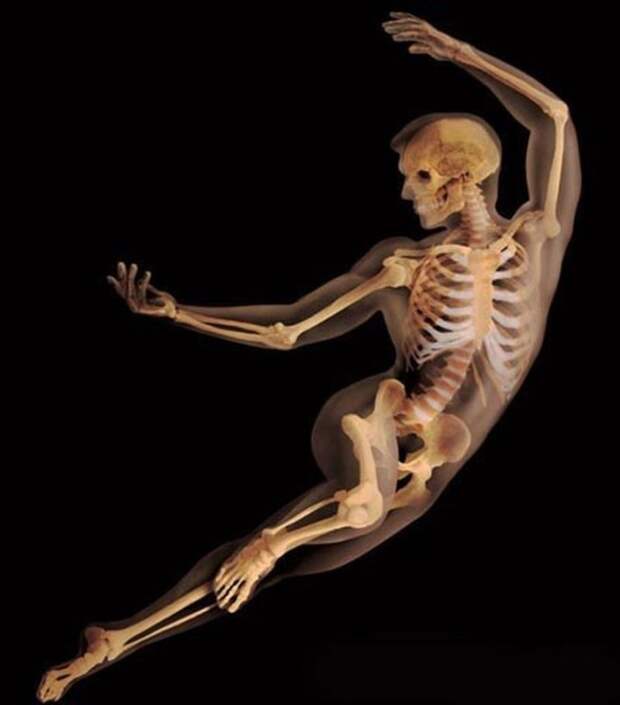

Естественная красота изгибов